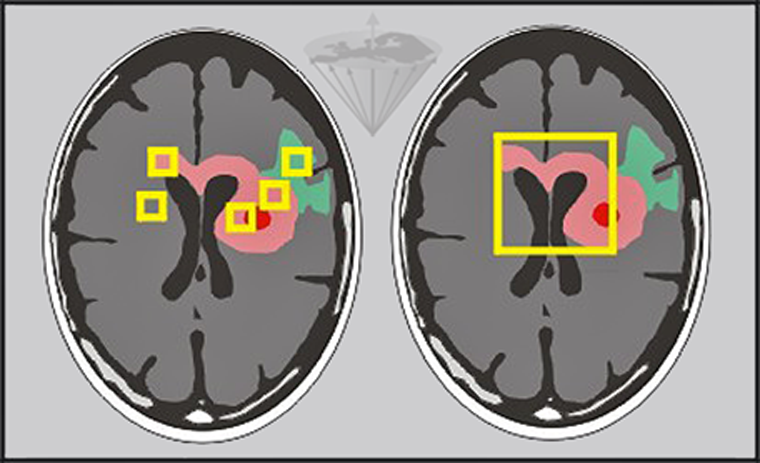

Otras posibles fuentes de error son la desviación estándar de los ajustes, los artefactos y las variaciones en la selección de elementos del volumen hechas por los operarios (Figura 04-21).

Figura 04-21:

Se pueden hacer mediciones de los tiempos de relajación in vivo ya sea pixel por pixel o por regiones de interés de diferente tamaño.

Izquierda: Pequeñas regiones de interés en edema (verde), tumor (rosado) y necrosis (rojo) y otras patologías.

Derecha: Una región más grande que cubre las principales partes del tumor.

Además, lesiones similares pueden tener más de un tiempo de relajación exponencial, e.g., los tumores cerebrales y las placas de esclerosis, lo cual no es inesperado teniendo en cuenta la naturaleza heterogénea de los tumores — y de los tejidos en general.

La reproducibilidad de estas mediciones también es limitada.